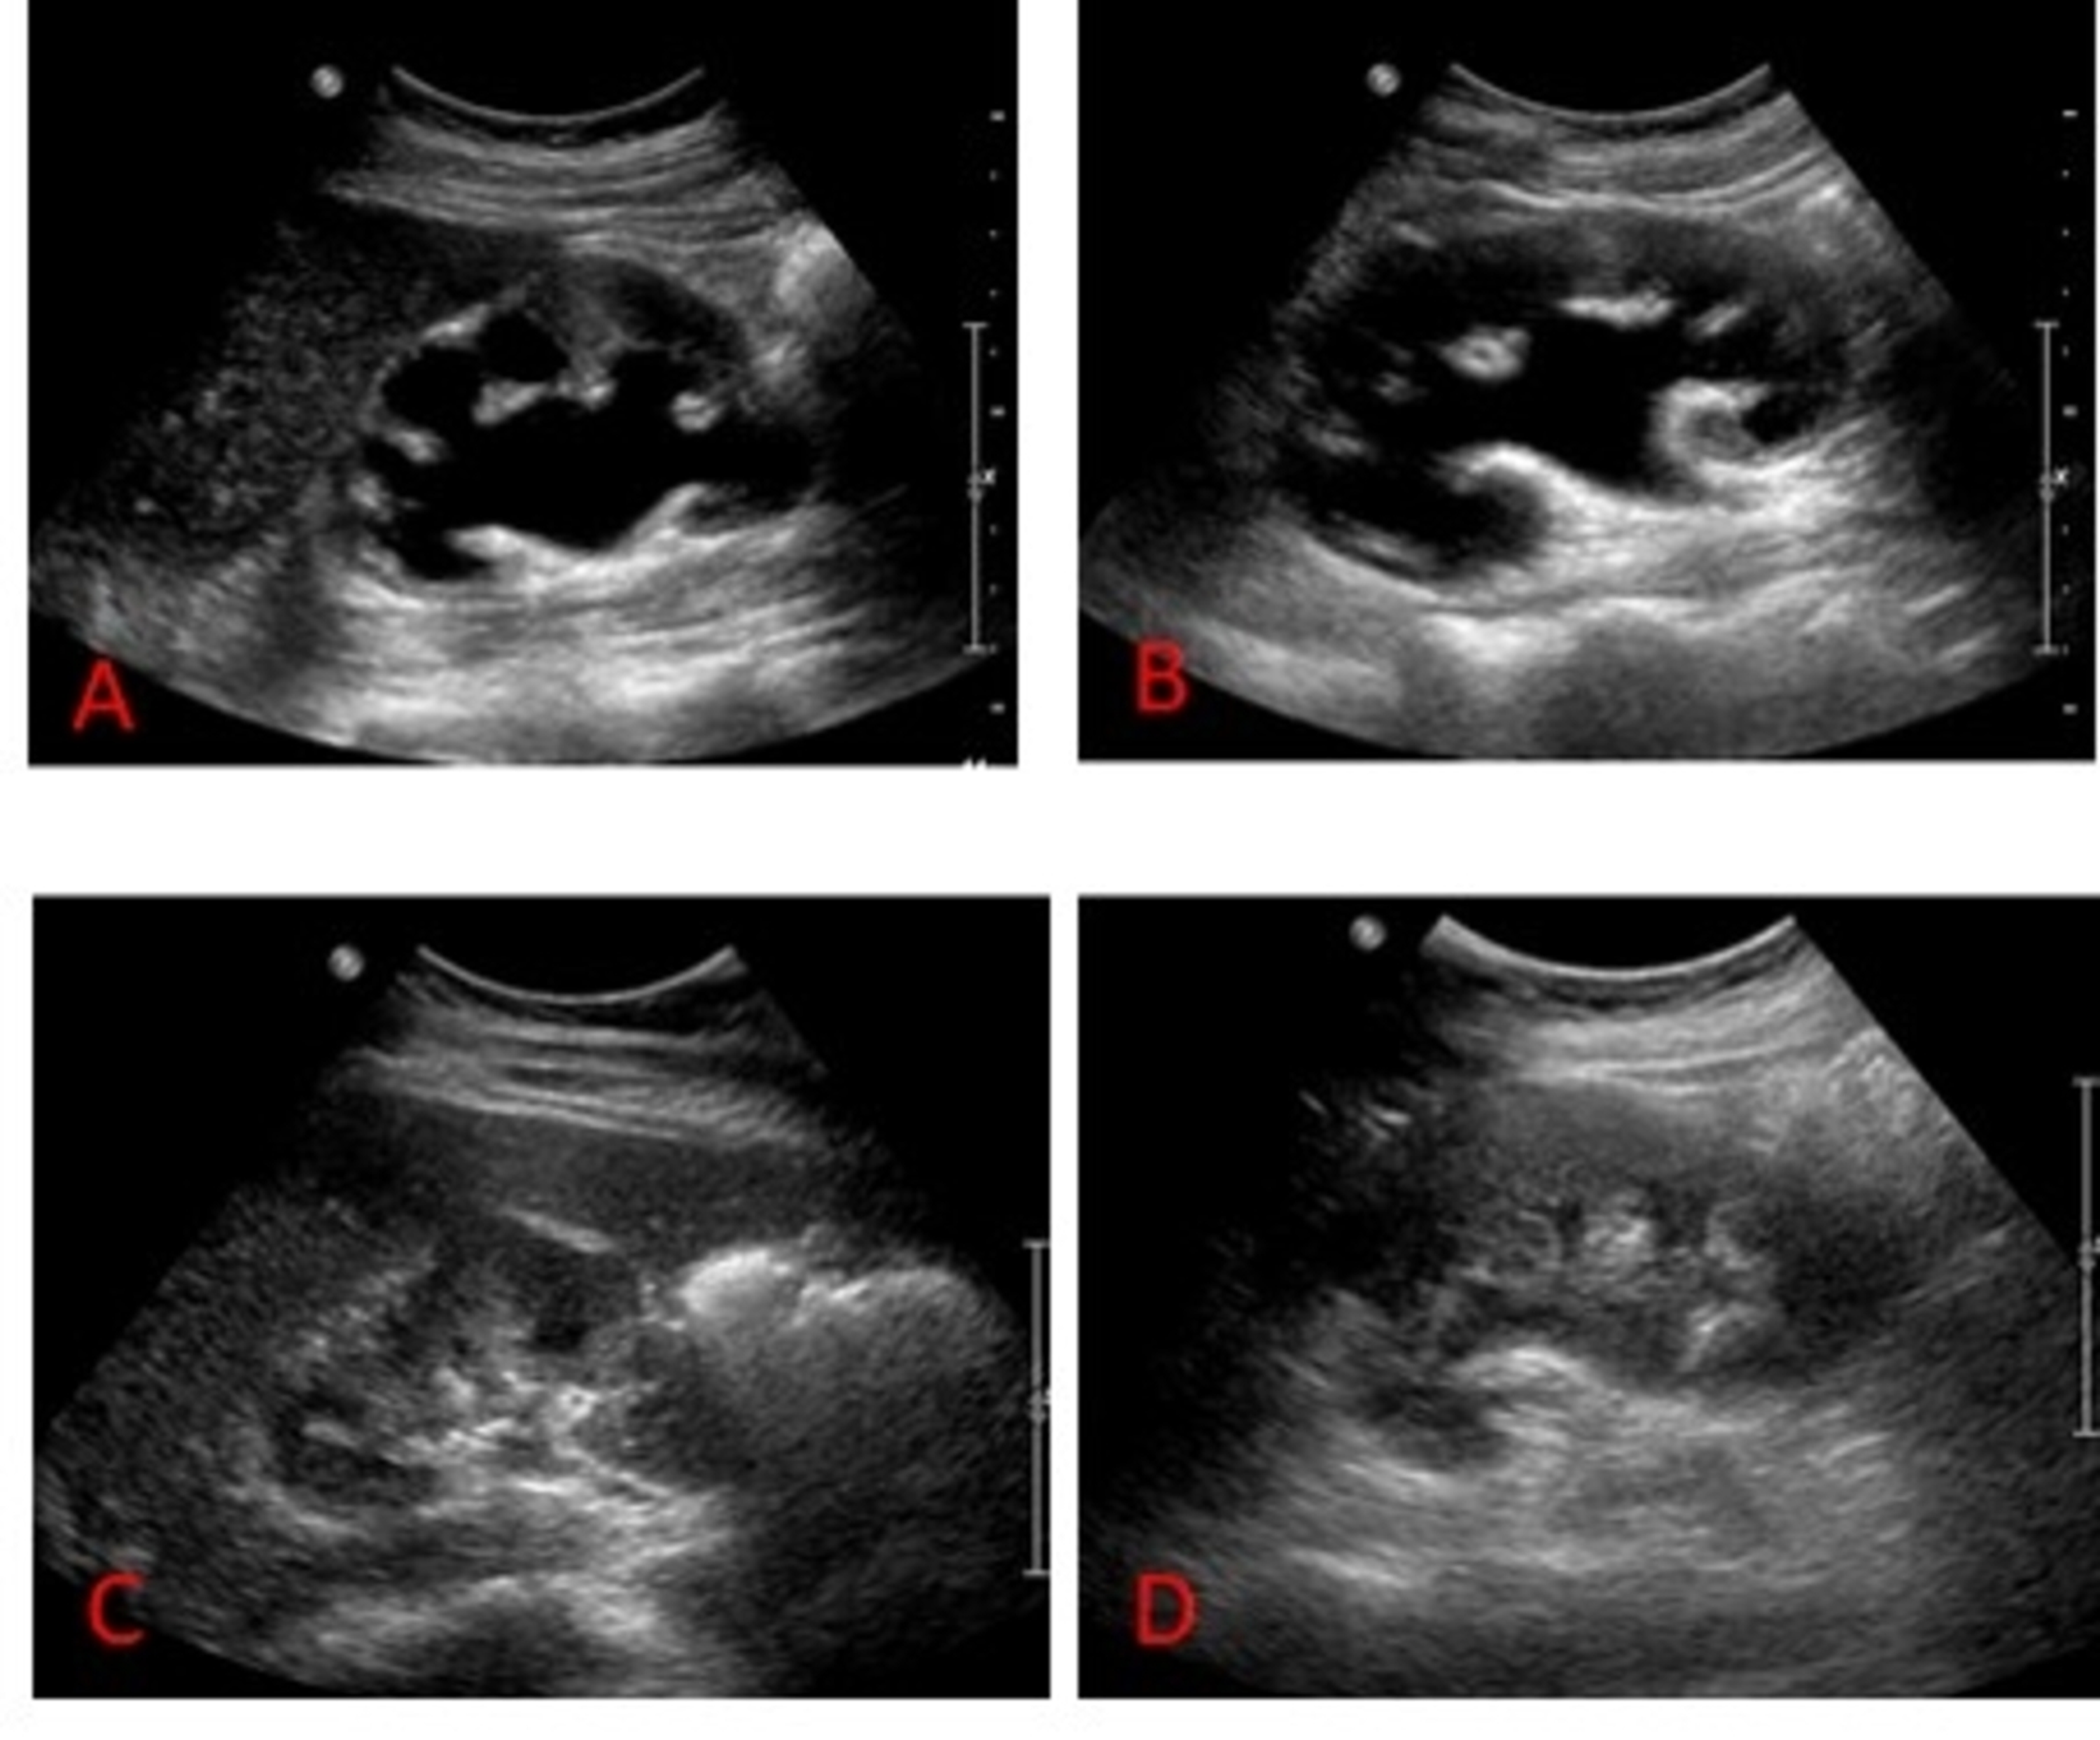

Nephrostomy Tube Ultrasound Nephrostomy Tube Placement Complications The most common complication that you’re likely to encounter is infection. This review summarizes the existing literature and provides a framework for emergency providers regarding the evaluation and. Pain, swelling, or redness at. You should contact your doctor immediately if you experience. Recognize clinical benefits that can be achieved. Placing a nephrostomy tube is generally a safe procedure. Signs of. Nephrostomy Tube Placement Complications.

Nephrostomy Tube Ultrasound Nephrostomy Tube Placement Complications Placing a nephrostomy tube is generally a safe procedure. Pleural injury is possible during nephrostomy tube placement. The most common complication that you’re likely to encounter is infection. Signs of potential nephrostomy tube complications include: Pain, swelling, or redness at. Identify complications from percutaneous nephrostomy. Recognize clinical benefits that can be achieved. This review summarizes the existing literature and provides. Nephrostomy Tube Placement Complications.